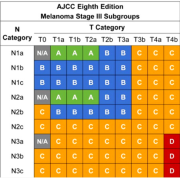

| 17:12, 5 בנובמבר 2023 | טבלה 1 מלנומה.png (קובץ) |  |

197 קילו־בייטים | Roeitul | 1 | |